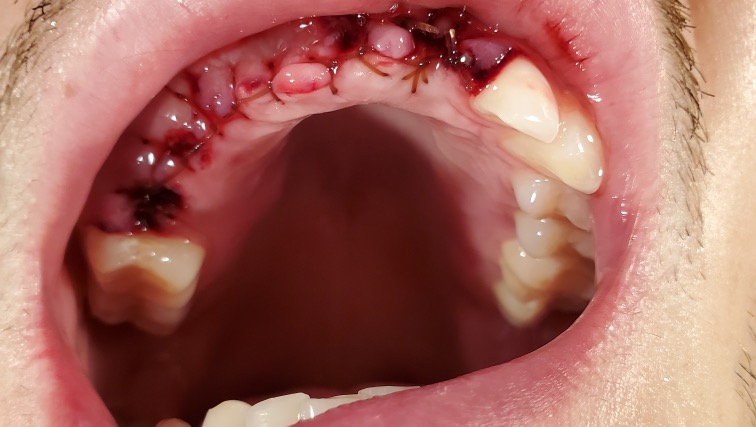

Early in the morning of June 12th, my sister received a call from Pennsylvania State Police that my little brother Jeffrey was found on the side of a dirt road near our cabin in Confluence, Pa. His throat had been slit open and there was severe damage to his face and massive blood loss. We were unsure if he was going to survive. Because of the severe trauma to his face, unfortunately he has no memory of what happened. He suffered a 4 inch laceration to the neck, 2 broken orbital bones, a broken nose, multiple jaw fractures, is missing 9 teeth, and dozens of other less severe injuries.

The state police have since closed the investigation and state that he “fell”. Because we have no answers and thanks to the police has been ruled a fall instead of attempted murder, dental insurance will not cover the cost of the teeth replacement.